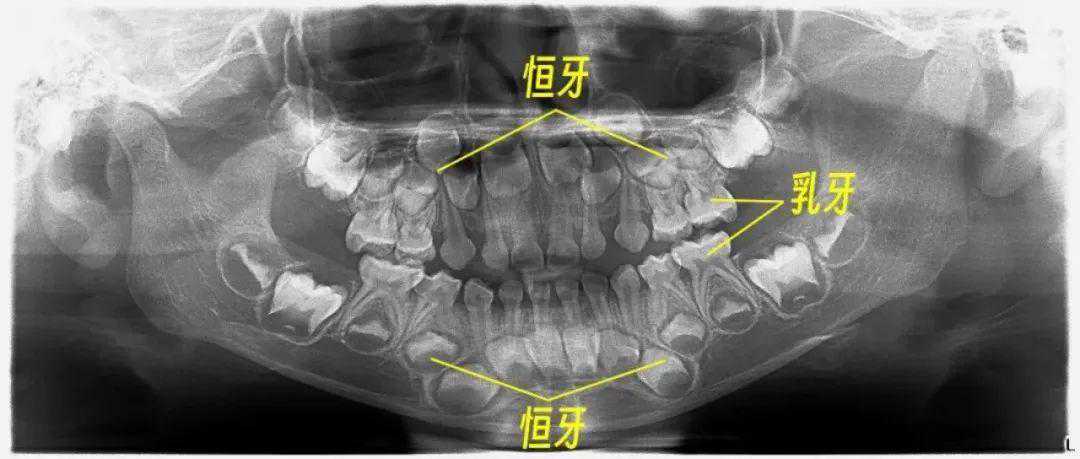

在出生前,20颗乳牙基本形成,只是还未萌出;

直到出生6个月之后,乳牙依次萌出;

恒牙也不是6岁后才开始生长的,而是从胚胎第4-5个月时,牙胚就开始发育了。

▲5岁孩子的口腔全景片(影像放射科邓志强医师提供)